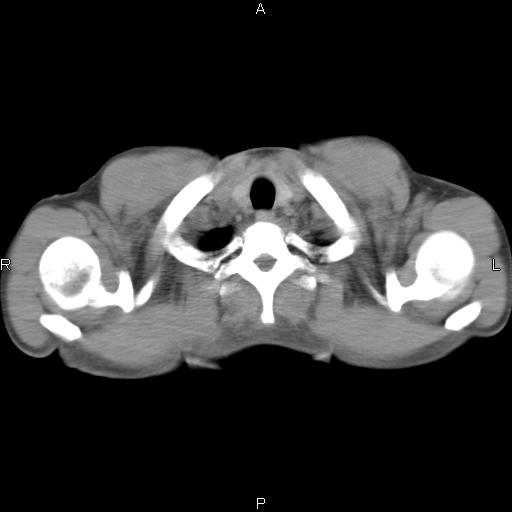

患者,男,40岁。间断发热,咳嗽二十余日。体温最高达38.9° 在当地诊所抗炎治疗三天后体温降至正常,患者自行停药。今又发热。胸片示,左下肺阴影。

左下肺片状高密度影,境界模糊,密度不均,考虑感染性病变可能性大,建议抗炎治疗后复查。左肺门增大,不除外占位性病变,必要时支气管镜检。

建议强化或纤支镜观察,考虑肿瘤性病变可能性大